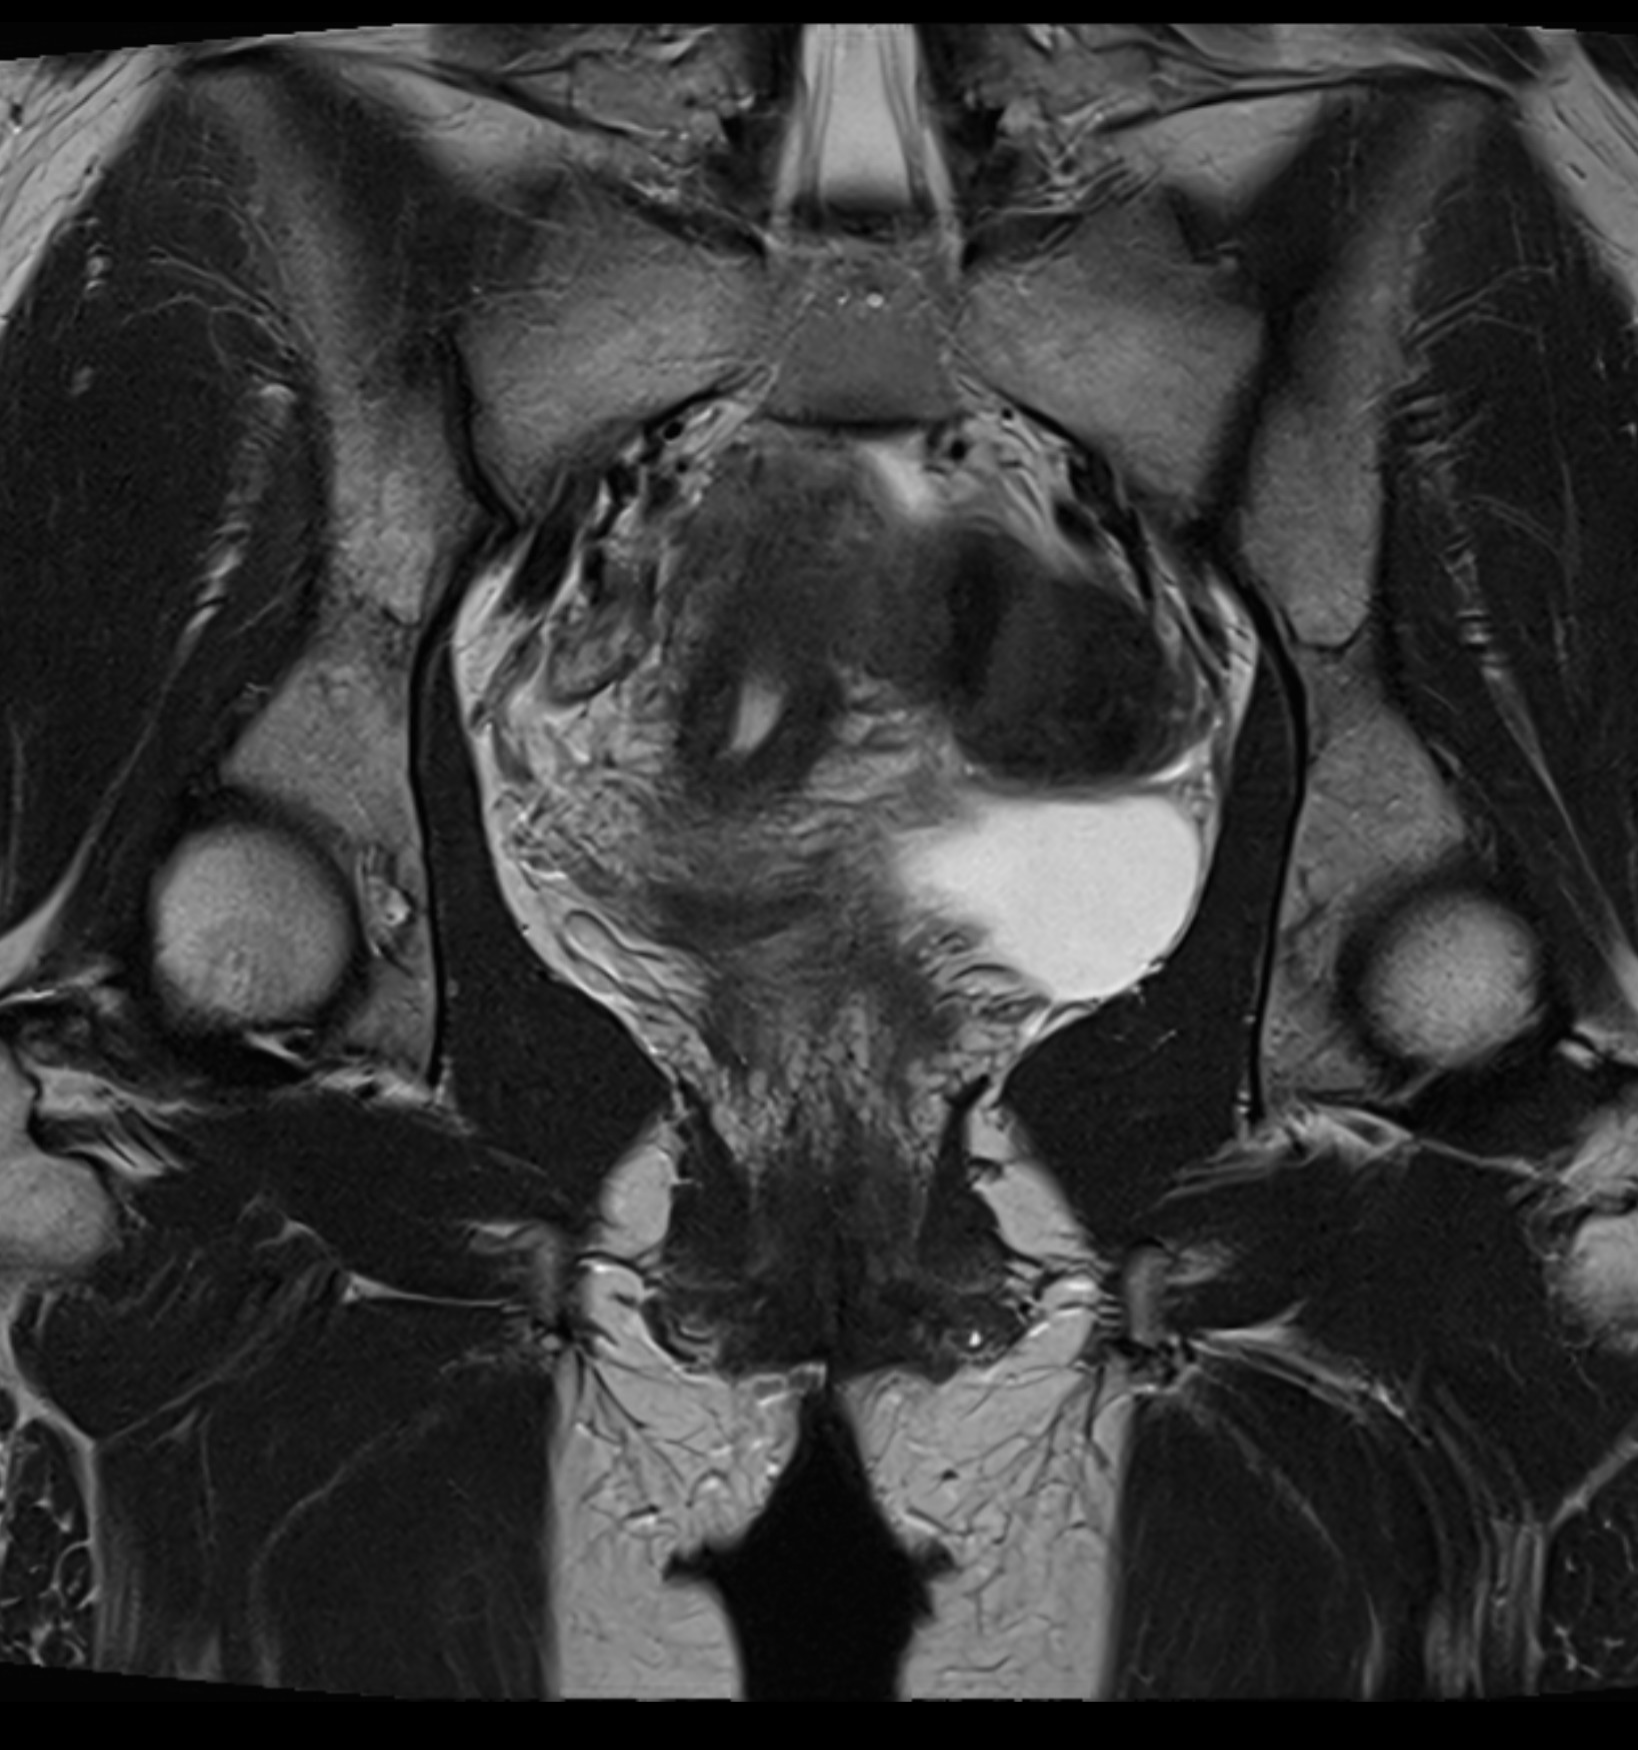

MRI Pelvic – for gynecological problems, cysts or suspected endometriosis

If you have pain in the lower abdomen, irregular bleeding, fertility problems or suspect that something is not right in the lower abdomen, an MRI examination of the pelvis can be the next step to get the right diagnosis. MRI pelvic, also called MRI gynecology, is a painless and radiation-free examination that provides very detailed images of both the uterus, ovaries and fallopian tubes.

The examination is used when other methods such as ultrasound or gynecological examination have not been able to explain your symptoms. With the help of MRI, conditions such as endometriosis, fibroids, cysts, tumors, malformations or effects on nearby organs such as the bladder or intestines can be detected. It is also an important method before fertility treatment or in preparation for surgery.

Whether you are seeking answers to long-term symptoms or following up on previous findings, pelvic MRI gives you and your doctor a clear picture that can form the basis for the right treatment and continued care.